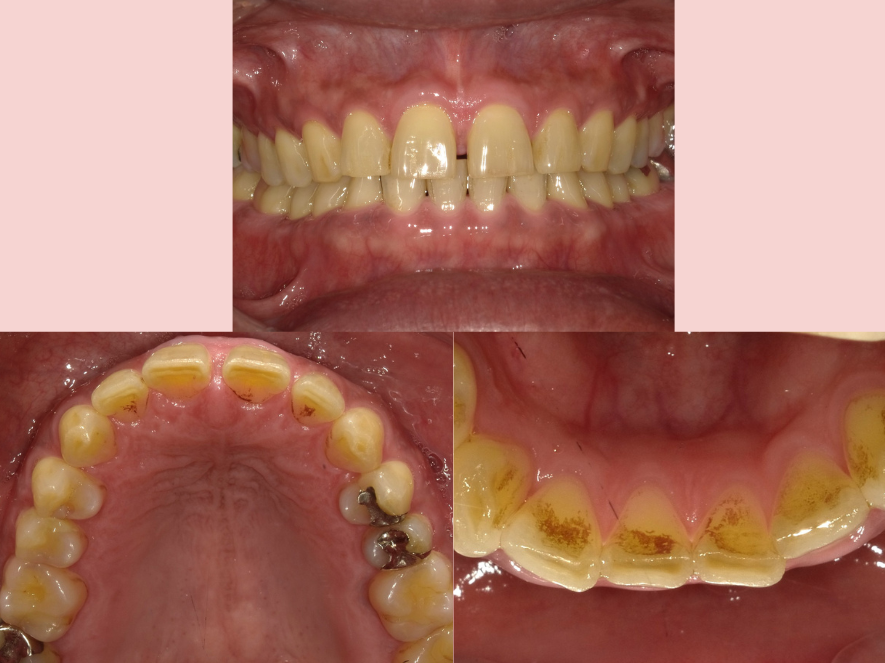

治療前

| 治療名称 | エアフロー+PMTC |

|---|---|

| 年齢・性別 | 50代・男性 |

| 主訴 | メンテナンス前に着色を落として綺麗にしたい。 |

| 期間 | 1回 |

| 費用 | 5.500円 |